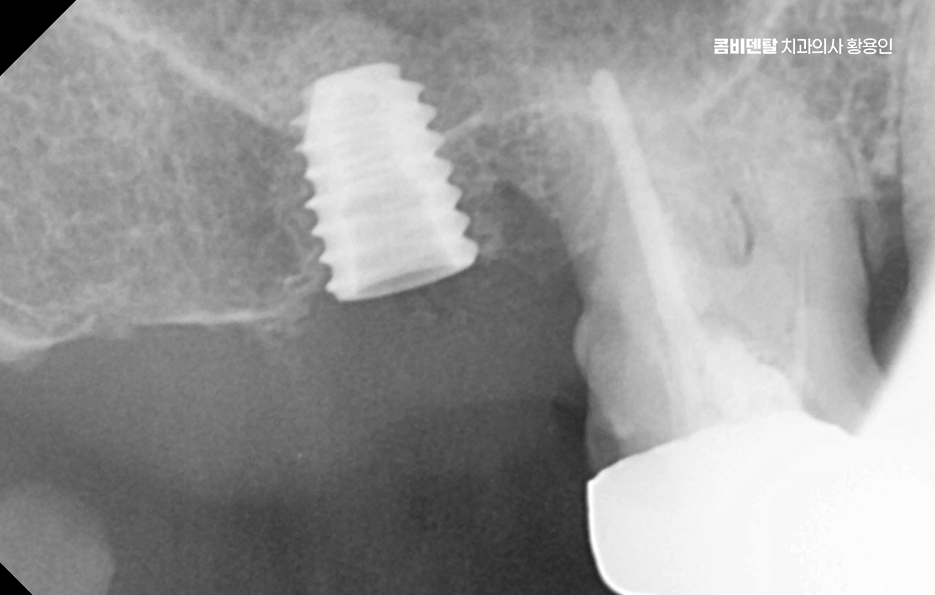

치아 발치 후 임플란트 치료 과정을 살펴보면 임플란트는 티타늄이라는 재료로 만든 인공 치근을 잇몸 뼈에 식립하고, 그 위에 보철물을 올리는 구조로 티타늄은 인체에 잘 맞는 재료라 뼈와 자연스럽게 붙는 성질이 있는데 이 과정을 ‘골융합’이라고 하고 이 골융합이 안정적으로 일어나야만 임플란트가 오래 버틸 수 있고, 자연치아처럼 역할을 할 수 있는 거예요.

일반적으로 발치 후 뼈 상태가 양호하다면, 약 2~3 개월 정도의 치유 기간을 거친 다음 임플란트를 심게 되는데 요즘은 상황에 따라 바로 임플란트를 식립하는 ‘즉시 식립’ 방식도 많이 사용되고 있으며 단, 이러한 치료 방식은 뼈의 상태가 충분히 튼튼하고 염증이 없는 경우에 가능하며 경험 많은 치과의사와 함께하는 것도 중요할 수 있었어요

치아 발치 후 임플란트 치료 과정은 처음에 CT나 파노라마 엑스레이를 통해 뼈의 양과 밀도, 신경 위치를 정확히 확인하는 것부터 시작되며 치아가 빠진 자리에 뼈가 많이 흡수되어 있다면, 임플란트를 심기 전에 뼈이식을 먼저 해야 할 수 있지만 반대로 뼈 상태가 좋다면 임플란트를 심고, 보통 3개월 동안 뼈와 잘 붙을 때까지 골융합 과정을 기다리게 되며 골융합이 잘 이루어진 뒤에는 그 위에 지대주라는 연결 부품을 끼우고, 그 위에 최종 보철물을 씌우면서 치료가 마무리되고 있어요